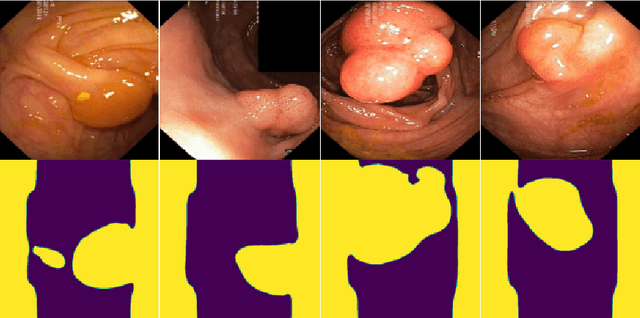

Abstract:Generalizability is seen as one of the major challenges in deep learning, in particular in the domain of medical imaging, where a change of hospital or in imaging routines can lead to a complete failure of a model. To tackle this, we introduce Consistency Training, a training procedure and alternative to data augmentation based on maximizing models' prediction consistency across augmented and unaugmented data in order to facilitate better out-of-distribution generalization. To this end, we develop a novel region-based segmentation loss function called Segmentation Inconsistency Loss (SIL), which considers the differences between pairs of augmented and unaugmented predictions and labels. We demonstrate that Consistency Training outperforms conventional data augmentation on several out-of-distribution datasets on polyp segmentation, a popular medical task.